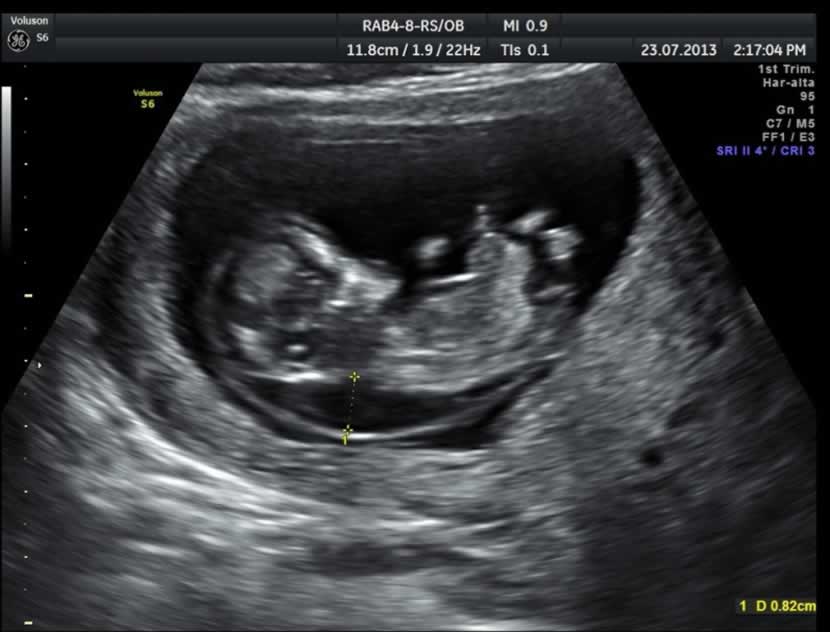

- Una ecografía entre las semanas 11-13.6 de embarazo:

> Para examinar el hueso nasal